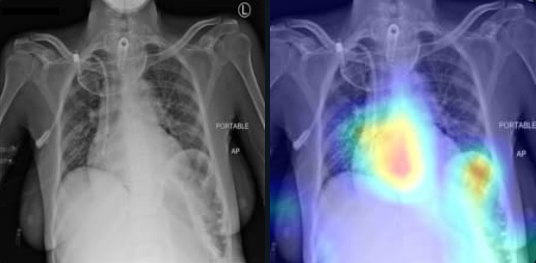

The Grad-CAM mappings of our 3-layer headed SwinCheX for samples containing Consolidation, Atelectasis, Mass or Cardiomegaly are provided in the Figure 3. Lung consolidation can be easily seen on an X-ray image by the naked eye. The consolidated parts of the lung look white, or opaque, on a chest X-ray. In Figure 3a our model detects these parts and diagnoses the sample as positive. Furthermore, an X-ray image can be helpful in the diagnosis of Atelectasis. Findings on an X-ray suggestive of Atelectasis include displacement of fissures, rib crowding, the elevation of the ipsilateral diaphragm, volume loss on ipsilateral hemithorax, hilar displacement, and compensatory hyperlucency of the remaining lobes. In Figure 3b, our model has diagnosed this disease by looking at the bottom of the two lungs and their relative positions.

Refer to caption

(a) Consolidation

Figure 3: Grad-CAM of our model for positive samples containing Consolidation, Atelectasis, Mass, or Cardiomegaly. For each sample, the original image is shown on the left and the Grad-CAM of the 3-layer headed SwinCheX is shown on the right.